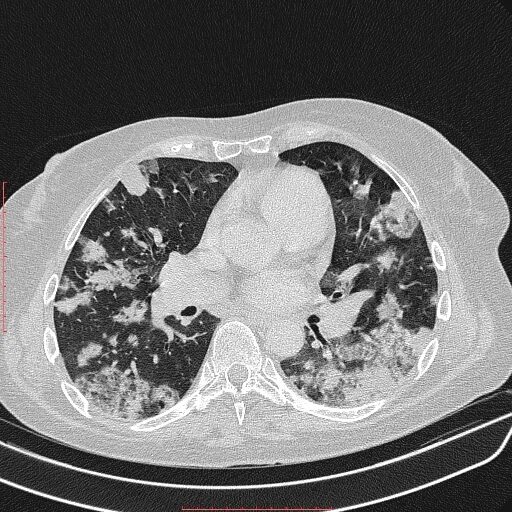

Аденокарцинома легких 4 стадия прогноз